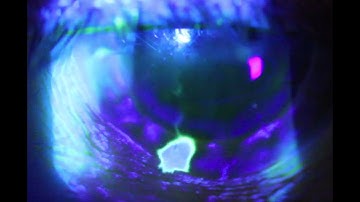

Seidel Test video capture using QuikVue Smartphone Eye Imaging Adaptor